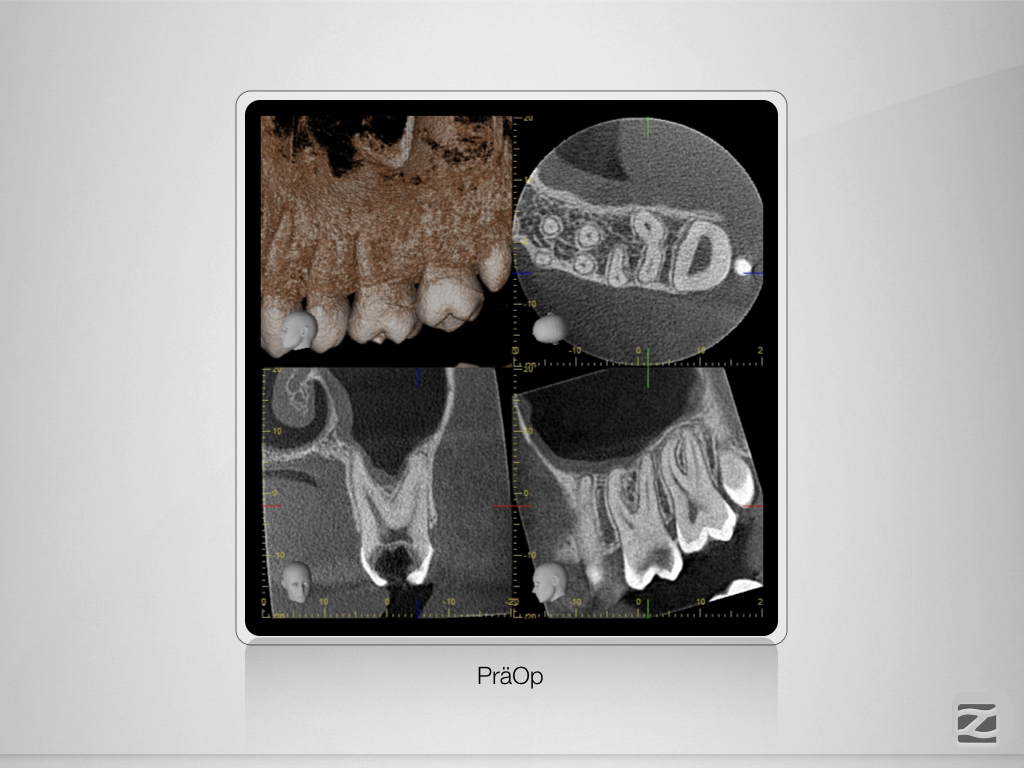

26D.002

Alternativlos?